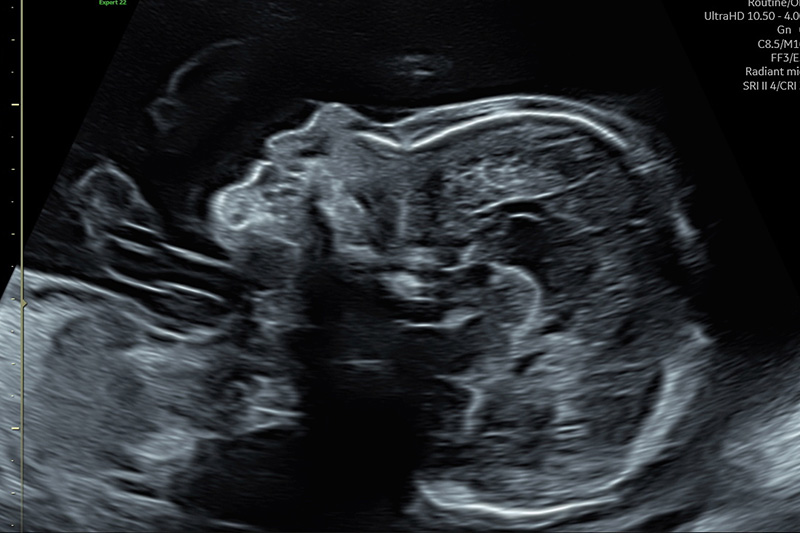

Der beste Zeitpunkt ist die 20.-22. Woche der Schwangerschaft.

ist es, Informationen über die Schwangerschaft und den Zustand des ungeborenen Kindes zu erhalten. Es werden die einsehbaren Organe (Gehirn, Herz, Nieren, Wirbelsäule, Extremitäten, ...) hinsichtlich ihrer korrekten Ausbildung und zeitgerechten Entwicklung untersucht.

So können häufig Gefährdungen des ungeborenen Kindes frühzeitig erkannt werden, und es kann eventuell hilfreich eingegriffen werden: